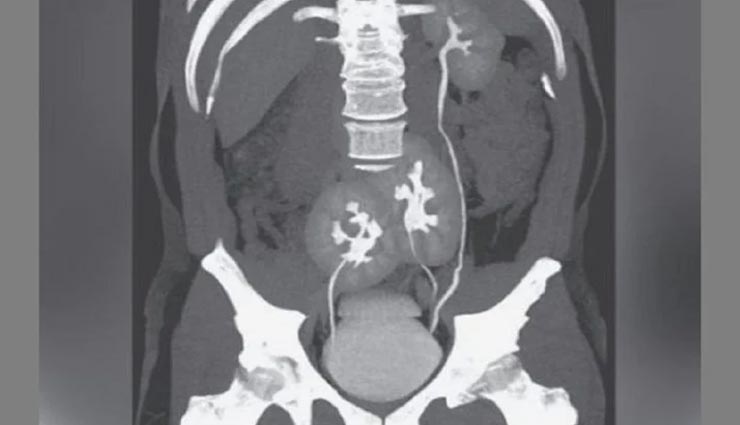

कुदरत के चमत्कार के सामने इंसान कुछ भी नहीं कर सकता और ऐसा मेडिकल इतिहास में कई बार देखने को मिला। आज इस कड़ी में हम एक ऐसी ही अनोखी घटना की जानकारी लेकर आए हैं जिसके अनुसार ब्राजील के एक व्यक्ति के शरीर में दो नहीं बल्कि तीन किडनी पाई गई हैं और हैरानी की बात यह है कि उसे किडनी से जुड़ी किसी प्रकार की परेशानी नहीं हैं। सभी किडनी सामान्य तरीके से काम कर रही हैं। 38 साल के इस व्यक्ति को पेट के निचले हिस्से में तेज दर्द शुरू होने के बाद यह मामला सामने आया। पेट दर्द से पीड़ित यह व्यक्ति जब डॉक्टर के पास पहुंचा और तो डॉक्टर ने उसका सीटी स्कैन कराने को कहा। सीटी स्कैन में ही पता चला कि उसके शरीर में तीन किडनी है। यह व्यक्ति ब्राजील की राजधानी साओ पाउलो का रहने वाला है।

न्यू इंग्लैंड जर्नल ऑफ मेडिसिन पत्रिका में इस संबंध में प्रकाशित रिपोर्ट के मुताबिक, व्यक्ति को स्लिप डिस्क की समस्या थी। अस्पताल में डॉक्टरों ने स्लिप डिस्क का इलाज किया गया और फिर उसे छुट्टी दे दी गई है। डॉक्टरों के मुताबिक, मरीज के शरीर में किडनी से जुड़ी कोई समस्या नहीं मिली। व्यक्ति के शरीर में तीन किडनी पाए जाने के इस मामले से डॉक्टर भी हैरान है।